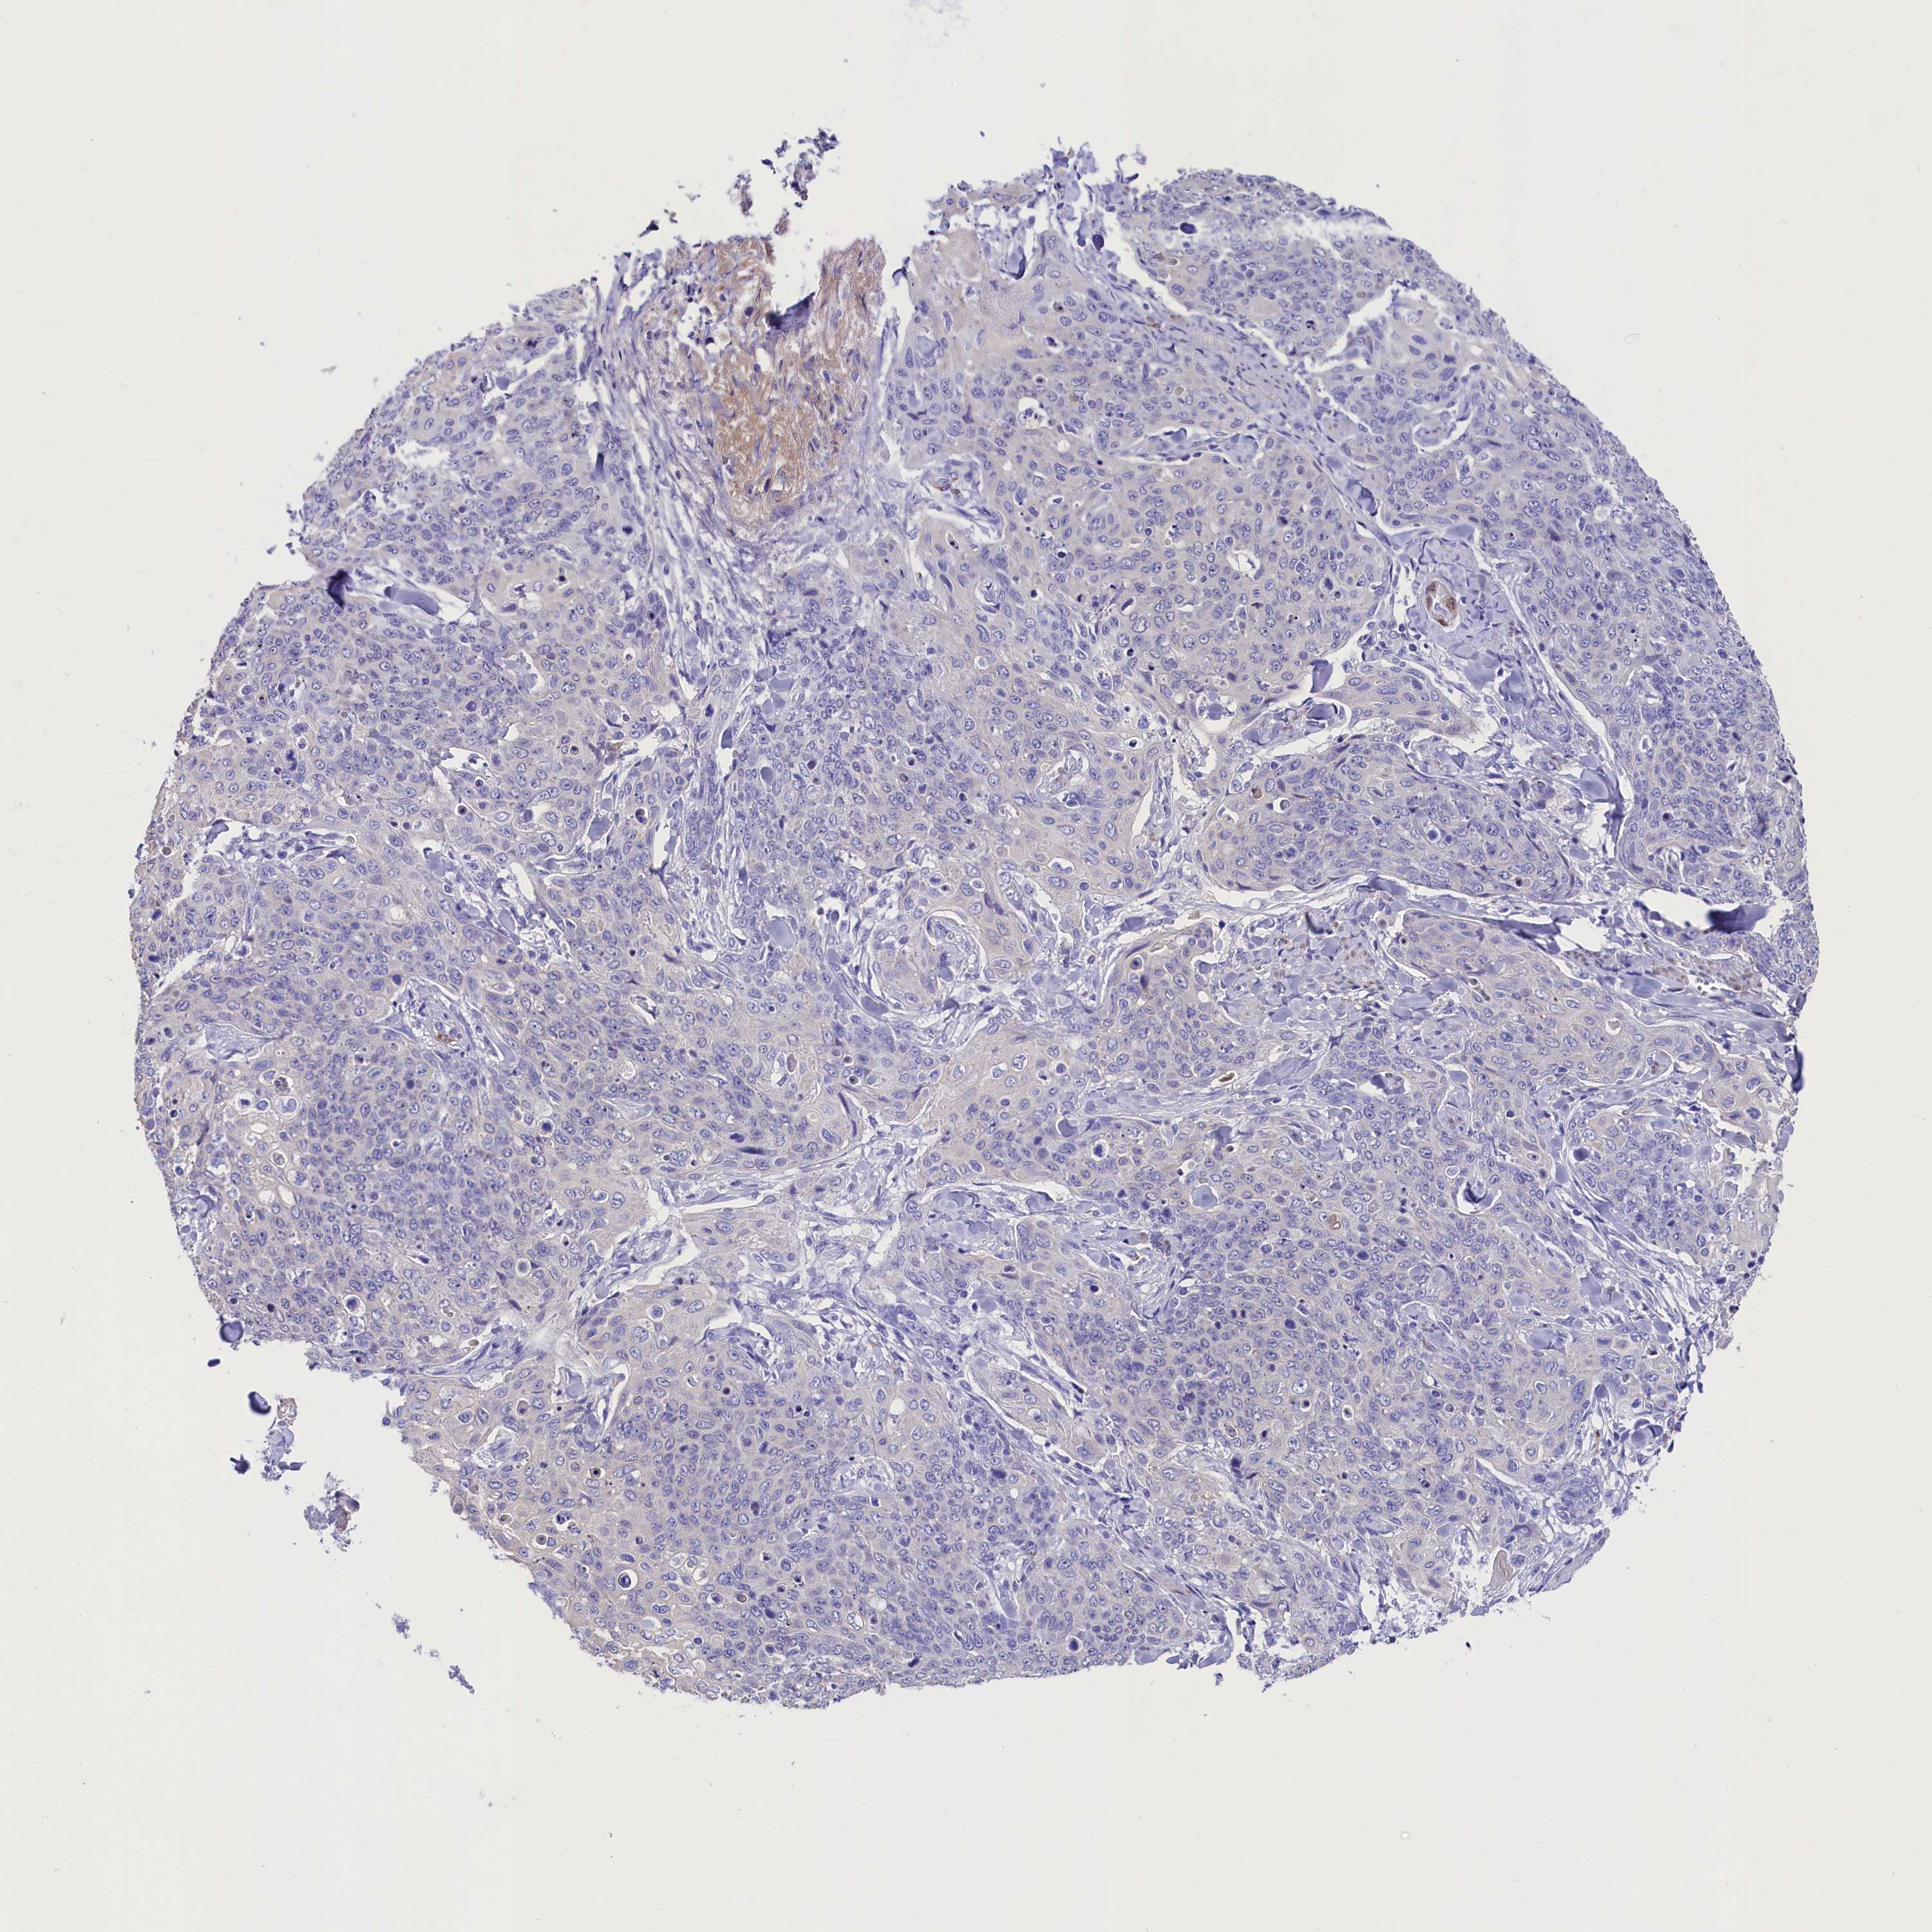

Basal cell and squamous cell cancer

SKIN CANCER - Protein expressioni

A mouse-over function shows sample information and annotation data. Click on an image to view it in a full screen mode. Samples can be filtered based on level of antibody staining by selecting one or several of the following categories: high, medium, low and not detected. The assay and annotation is described here.

Antibody stainingi

Antibody staining in the annotated cell types in the current human tissue is reported as not detected, low, medium, or high, based on conventional immunohistochemistry profiling in selected tissues. This score is based on the combination of the staining intensity and fraction of stained cells.

Each image is clickable and will lead to virtual microscopy that enables deeper exploration of all samples and also displays staining intensity scores, fraction scores and subcellular localization as well as patient and tissue information for each sample.

Antibody HPA042110

Staining

High

Medium

Low

Not detected

Intensity

Strong

Moderate

Weak

Negative

Quantity

>75%

75%-25%

<25%

None

Location

Nuclear

Cytoplasmic/membranous

Cytoplasmic/membranous,nuclear

Basal cell carcinoma

Squamous cell carcinoma, NOS

Squamous cell carcinoma, metastatic, NOS